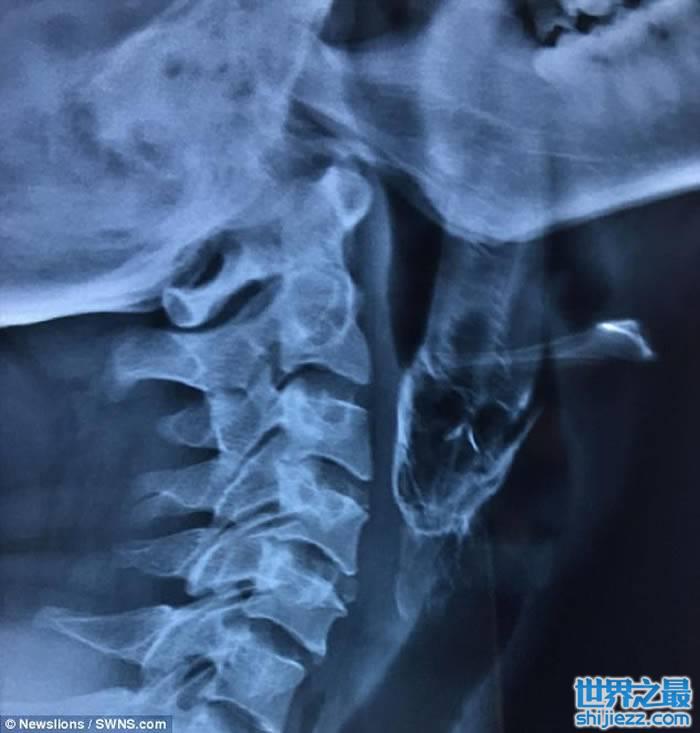

印度一名30岁男子早前意外将一条4吋长的活鱼吞下,导致不能呼吸及说话,需紧急送往医院。惟医生起初未能取出,需转送另一医院,医生最后成功用钳将鱼取出。

男事主达什(Santosh Dash)当日在池塘徒手捉了一条攀鲈,后者竟飞进他的口中,卡在喉咙,致几乎窒息。达什被送院后,医生设法取出活鱼但不果,需转送距达什村庄200米外的医院。

医生指,达什入院时,可从其口腔中望到鱼尾,随即送入急症室接受局部麻醉,再撑开其口用钳把鱼拉出。医生表示,达什的喉咙遭攀鲈割伤,需以鼻胃管喂食10天,现时已出院。